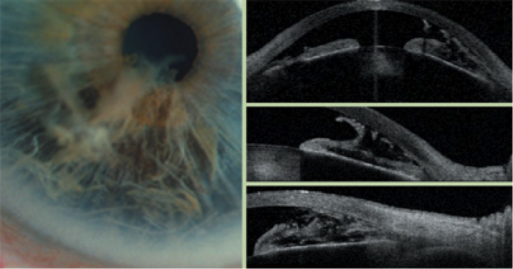

홍채층간분리, Iridoschisis는

1922년 Schmitt에 의해 처음보고된 질환으로,

보통 노년층에서 나타나는 일종의 퇴행성 변화로 알려져 있습니다.

홍채 실질의 양측성 분리가 특징적인 소견이며, 하반부에서 흔하게 발생합니다.